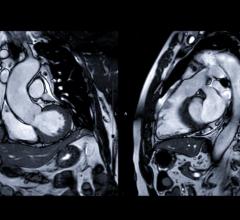

Contrast media, also called contrast agents, are used to enhance the blood and perfusion in tissues. This includes iodine based contrast for on computed tomography (CT), gadolinium based agents for MRI and lipid bubble contrast agents used in ultrasound.